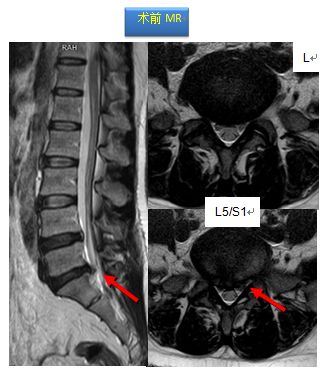

腰椎X线正位L5/S1间隙塌陷;核磁可发现L5/S1椎间盘后方偏右突出并压迫神经,同层面椎管狭窄。

结合患者的症状、体格检查及影像学资料,诊断为腰椎管狭窄症(L5/S1椎间盘突出并椎管狭窄)。

治疗方案:后路L5/S1减压植骨融合内固定术

该手术在梁徳主任指导下由江晓兵副教授按照标准化流程顺利完成,将致压物进行了彻底摘除,神经压迫顺利解除,并进行植骨及钉棒系统内固定。术后复查如下: